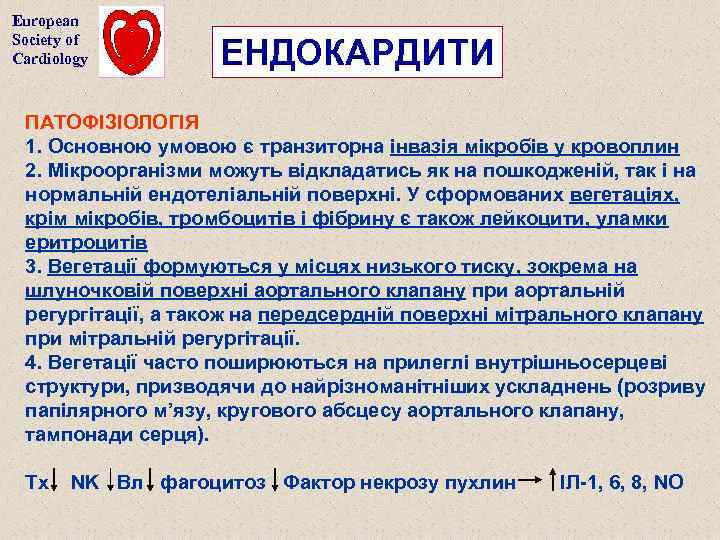

European Society of Cardiology ЕНДОКАРДИТИ ПАТОФІЗІОЛОГІЯ 1. Основною умовою є транзиторна інвазія мікробів у кровоплин 2. Мікроорганізми можуть відкладатись як на пошкодженій, так і на нормальній ендотеліальній поверхні. У сформованих вегетаціях, крім мікробів, тромбоцитів і фібрину є також лейкоцити, уламки еритроцитів 3. Вегетації формуються у місцях низького тиску, зокрема на шлуночковій поверхні аортального клапану при аортальній регургітації, а також на передсердній поверхні мітрального клапану при мітральній регургітації. 4. Вегетації часто поширюються на прилеглі внутрішньосерцеві структури, призводячи до найрізноманітніших ускладнень (розриву папілярного м’язу, кругового абсцесу аортального клапану, тампонади серця). Тх NK Вл фагоцитоз Фактор некрозу пухлин ІЛ-1, 6, 8, NO